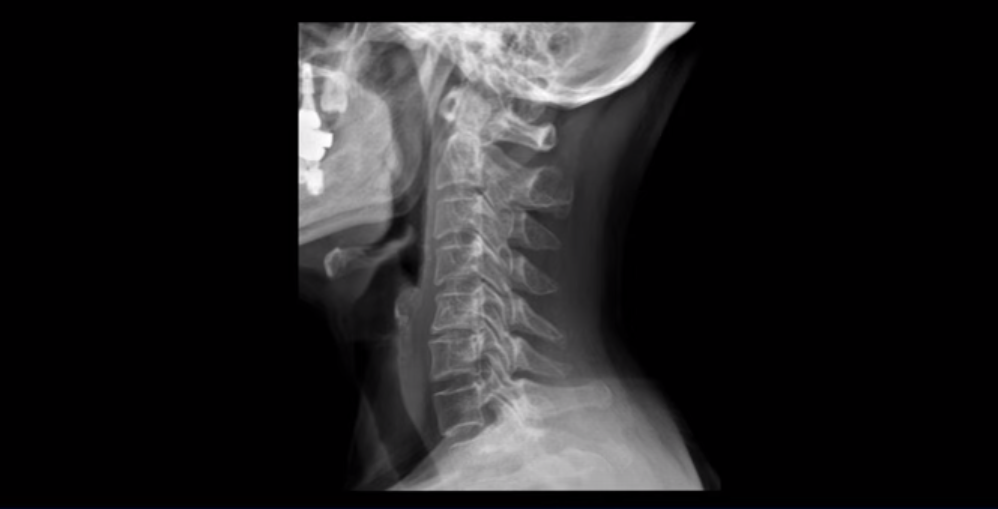

일반적으로 환자분들이 어지럽고 두통도 있고 하면 보통 이비인후과나 신경과에 많이들 가시는데, 목 문제 때문에 아픈 사람들은 당연히 이비인후과에서는 이상이 없다는 얘기를 듣고 또 신경과에서도 아무 이상이 없다고 듣거나 혹은 후두신경통을 진단받는 경우가 많습니다. 또 만성적으로 목과 어깨 근육이 뭉치면서 목 통증, 어깨통증이 있기 때문에 정형외과나 통증의학과, 한의원 등에 가면 근막통증증후군 같은 진단을 받는 경우도 많습니다. 게다가 이렇게 목이 아픈 환자분들은 척추병원에 가서 MRI를 찍어보면 이 환자분처럼 40세가 넘은 분들은 퇴행성 목디스크가 보이는 경우가 매우 많습니다.

이 환자분도 역시 이렇게 목디스크가 보이기 때문에 척추병원에서 목디스크 때문이라는 얘기를 듣고 신경 주사를 여러 번 맞게 되지만 목디스크 때문에 아픈 게 아니기 때문에 목디스크를 계속 치료해봐야 좋아지지 않는 겁니다.